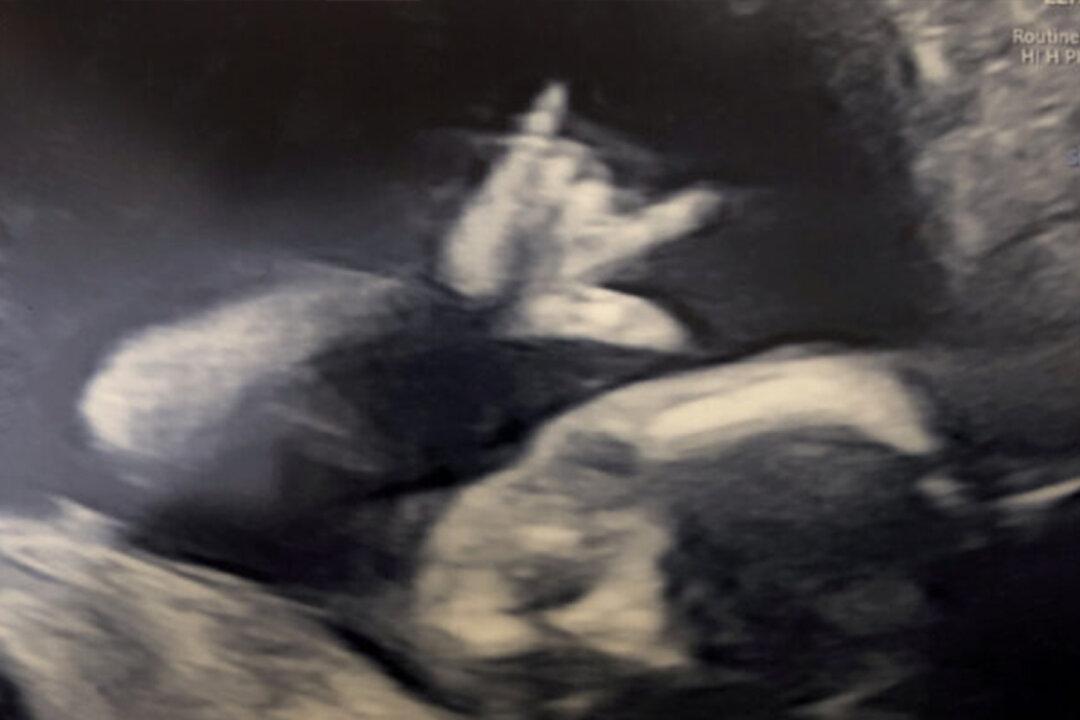

A rock fan dad was given a surprise performance after his unborn baby was seen making a heavy-metal sign in the womb during a baby scan.

Tom Dowie, 29, and fiancée Caitlin Welsh, 28, were at their week-19 scan on Nov. 2, 2019, when their unborn baby gave them the “sign of the horns.” The cheeky baby appeared to be holding up its index and little finger while holding its other fingers—looking exactly like the heavy metal rock sign.